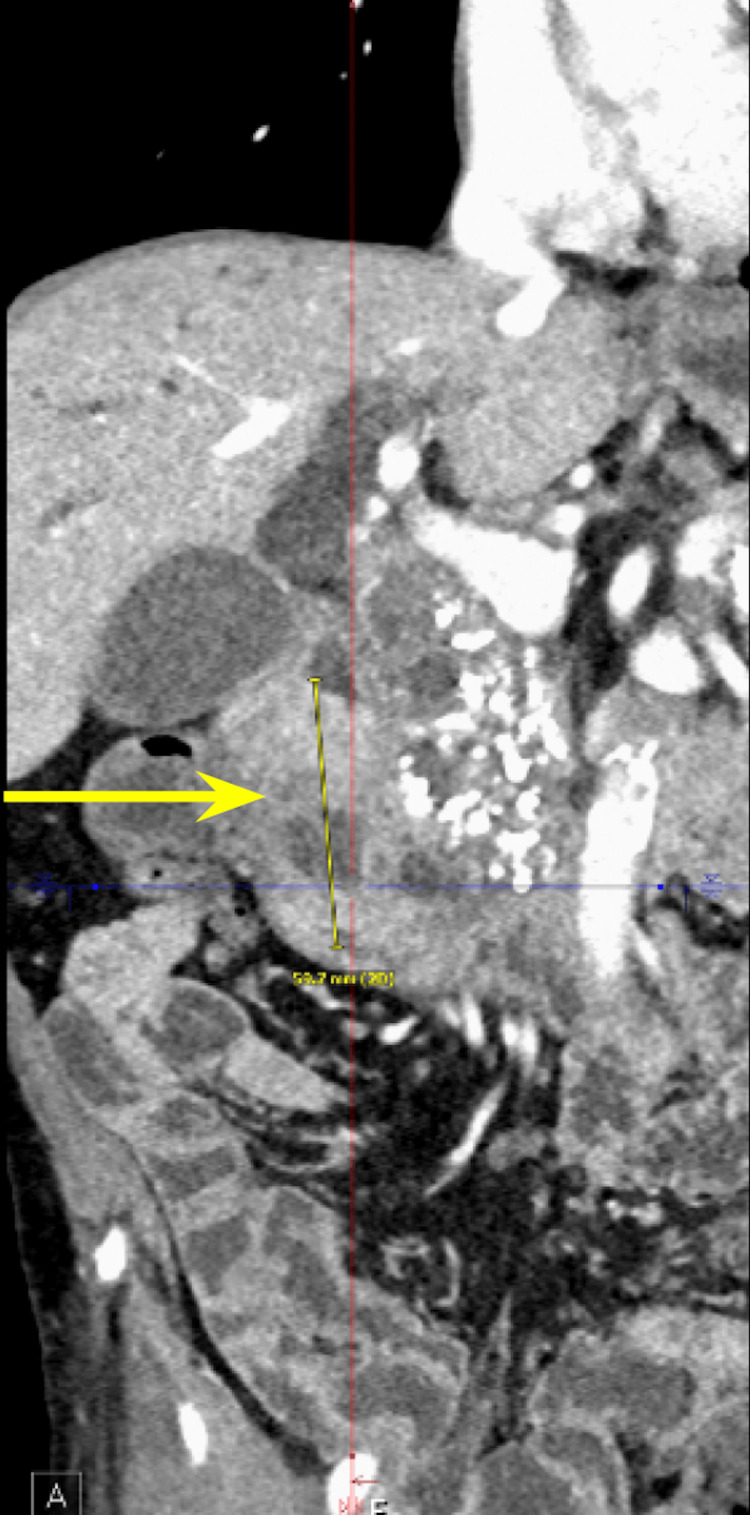

We present a case of a 68-year-old male with a past medical history of prostate cancer requiring radical prostatectomy, hypertension, hyperlipidemia, alcohol use disorder, and 50-pack-year smoking history who presented with several weeks of anorexia, dyspnea on exertion, generalized weakness, nausea, and vomiting. He also noted an unintentional 20-pound weight loss over the last several months. Vital signs were within normal limits with blood pressure of 118/80 mmHg, pulse of 98 beats per minute, respiratory rate of 16 while saturating 100% on room air, and temperature of 98.8°F. Physical exam was remarkable for a cachetic, ill-appearing male in no acute distress. Laboratory evaluation was significant for acute kidney injury (creatinine (Cr) of 2.89 mg/dL from baseline of 0.5-0.6 mg/dL; reference range: 0.51-0.96 mg/d), mild transaminitis with aspartate transferase (AST) of 46 IU/L (reference range: 14-33 IU/L), anion gap of 28 mmol/L (reference range: 4-16 mmol/L), lactic acidosis of 8 mmol/L (reference range: <2 mmol/L), and beta-hydroxybutyrate of 4 mmol/L (reference range: 0.5 mmol/L). CT of the abdomen and pelvis showed three main findings. The first was a large 6.0 cm heterogeneous mass located in the second portion of the duodenum and pancreatic groove (Figures 1–2).